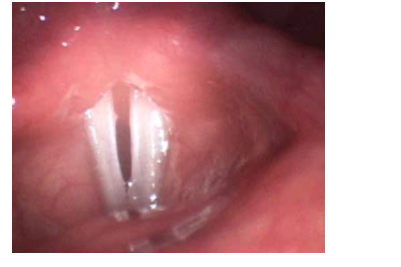

Vocal Nodules (BMA)

Occurs as a result of vocal abuse (yelling, singing, acting)

Maximum trauma occurs at junction of the anterior one third and posterior two thirds

Treatment is usually initially voice therapy. Surgery is a last resort.